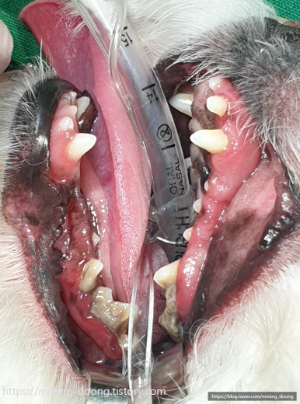

손쓸 수 없는 치아는 어쩔 수 없이 발치했고

치료가 가능한 이빨은 우선 최대한

치주염치료로 살려보자고 하셨다ㅠㅠ

아래쪽 어금니 상태가 가장 안좋아서

X-ray 찍어봐야 정확히 알 수 있지만,

혹시라도 턱뼈까지 손상되었을 경우에는

턱뼈골절 위험도에 대해 미리 얘기하셨다...